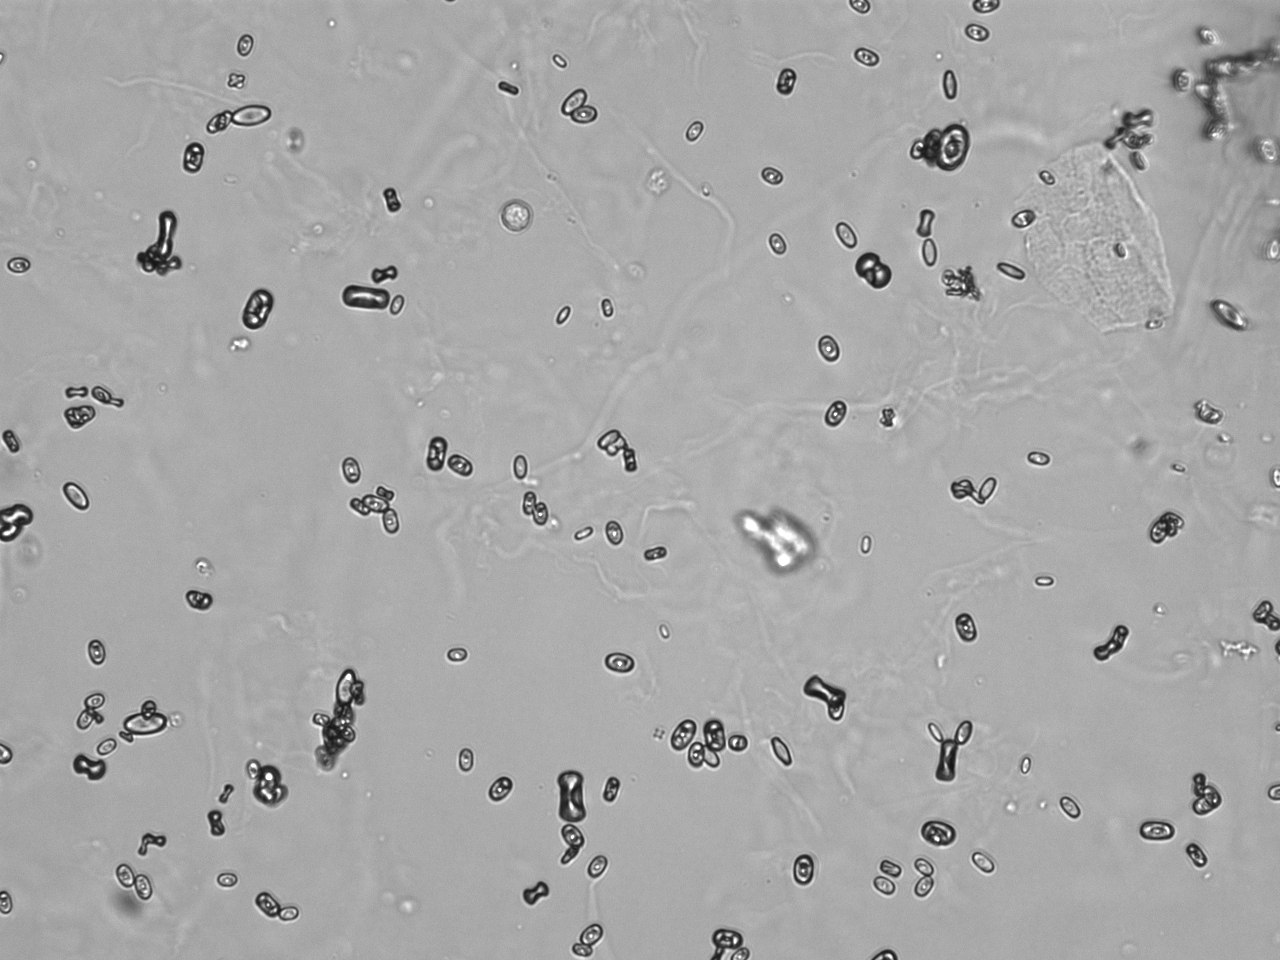

Urin-Feature: CaOxalateMonohyd